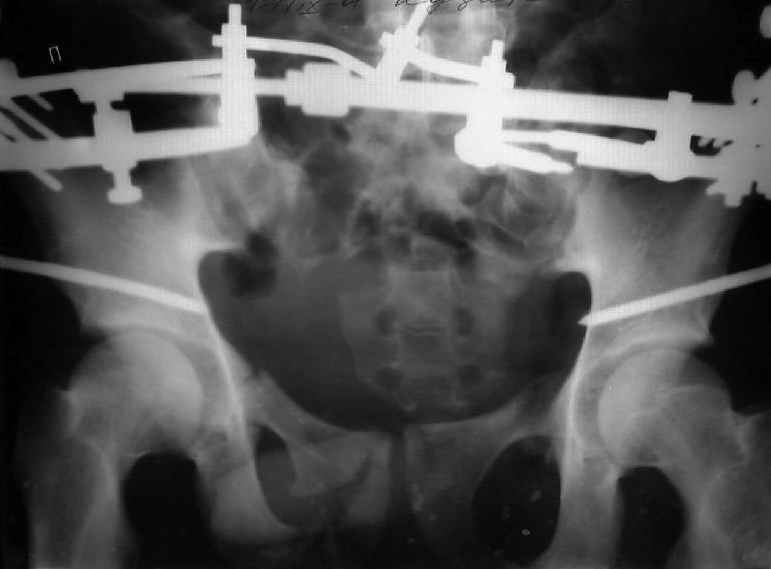

Застарелый перелом таза

Уважаемые коллеги! Хотел-бы обсудить варианты лечения больной с застарелым переломом таза. Возраст 40 лет. Травма 11 месяцев назад. Главный травматолог Камчатского Военно-морского госпиталя Юрий Алексеевич Булахтин

У больного судя по всему вертикальная деформация таза. А каковы основные жалобы пациента и какие у него функциональные требования?

Для информации к размышлению о возможности исправления имеющейся деформации предлагаю похожий случай.